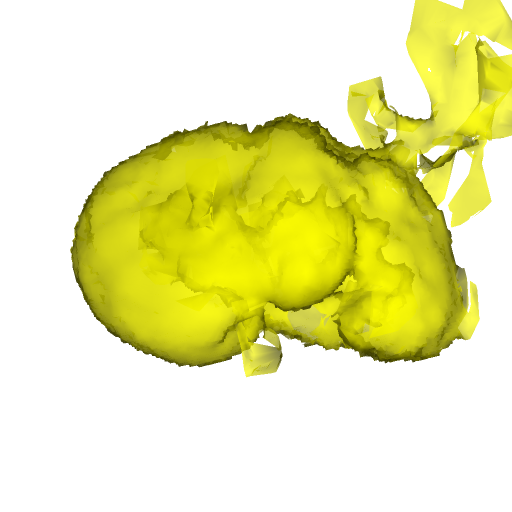

For MSER tracking, Donoser and Bischof [5] presented three different applications; license plate tracking, face tracking and the segmentation of a fiber network. In the third application, a fiber network is reconstructed in 3D by tracking a slice of the data along the axis orthogonal to the image data. Analogously, we track organs in slices of a Computed Tomography (CT) scan, to generate a 3D segmentation. We use the CT data provided in the 3DIRCADb dataset222The dataset is available on http://ircad.fr/research/3d-ircadb-01 [14].

To initialize the tracking process, the organ is segmented in an arbitrary slice of the CT data by a bounding box. The most stable MSHR is then selected in the initialization process for tracking. The respective MSHR is tracked through the slice data along the axis orthogonal to the image data. An example of the tracked regions is visualized for two examples in Fig. 7. Given the segmentations of the single slices, the organ can be reconstructed in 3D. We compare the reconstruction for MSER and MSHR tracking in Fig. 8. To enhance the visualization, the datapoints are triangulated and the surface normals calculated. Since the contrast of the organs can be very low in CT images, the MSER tracking has difficulties catching the organ boundaries. Furthermore, the organ is sometimes partely lighter and darker than the background, which may lead to MSER tracking failure. The proposed MSHR tracking copes well with these difficulties, and the reconstructions are significantly better.

Figure 7: Two examples sequences from the 3DIRCADb dataset [14]. Given an initial selection of a single slice (the middle image in (a) and (b)) of the organ, the proposed MSHR tracking tracks the region forward and backwards in space. The segmented slices can be used to reconstruct the organ, see Fig. 8 for an example reconstruction.

Figure 8: In the first row, the reconstruction of the liver is displayed for MSER tracking. The low contrast and the fact that the background is partly darker and lighter than the objects makes the reconstruction noisy. The proposed MSHR tracking can cope with these situations and the reconstruction is significantly better.